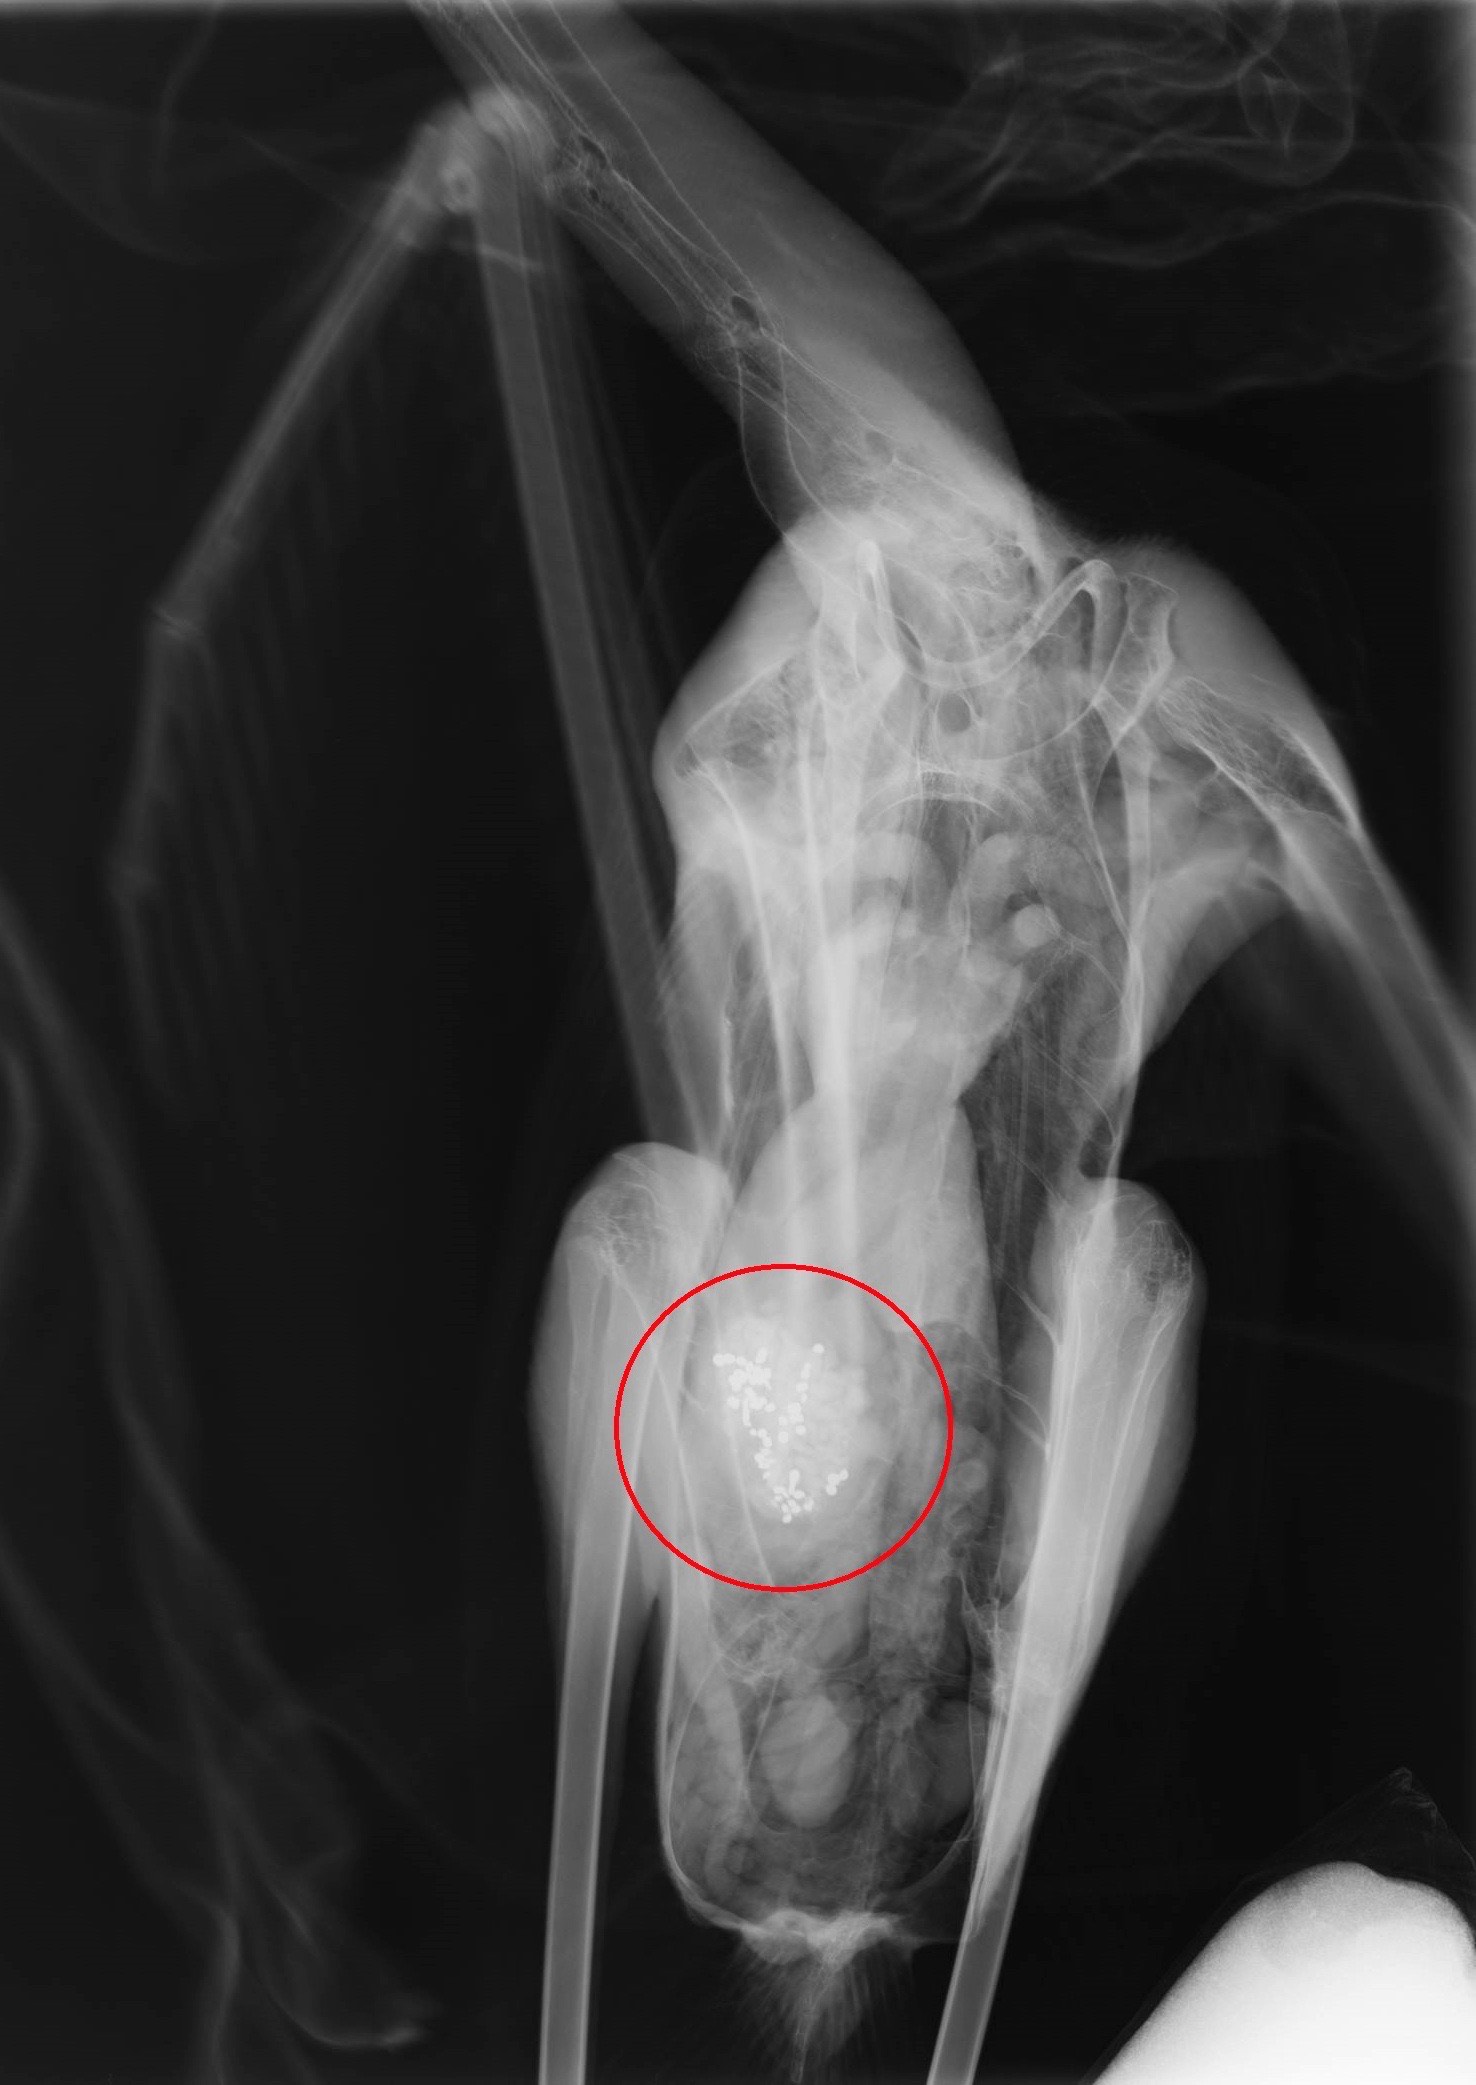

«Από τα τέλη Ιανουαρίου που παραλάβαμε τα δύο πρώτα φοινικόπτερα με συμπτώματα δηλητηρίασης, έως σήμερα έχουμε νοσηλεύσει στις εγκαταστάσεις μας συνολικά 9 πουλιά. Όλα τους είχαν καταπιεί σκάγια. Στην ακτινογραφία φαίνονται τα σκάγια στο στομάχι του πουλιού. Δεν είναι πυροβολημένο καθώς η νεκροψία έδειξε ότι τα είχε καταπιεί», σημείωσε ο κ. Καλπάκης.